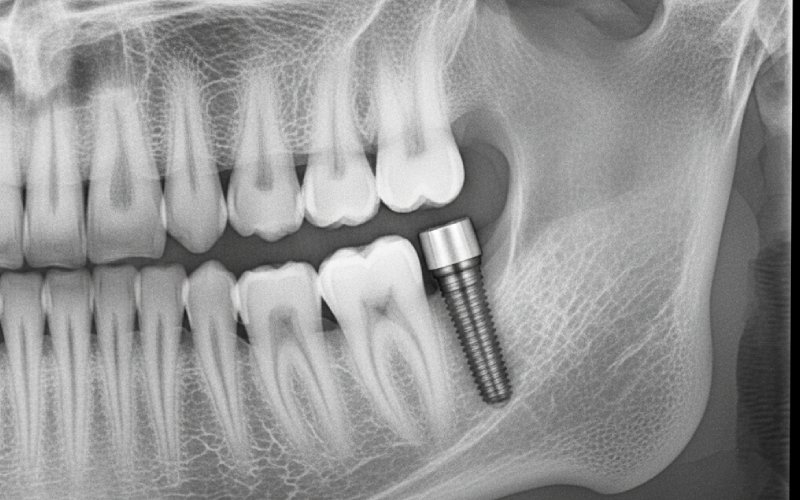

Et tandimplantat er den bedste måde at erstatte manglende tænder på. Du kan tænke på det som en menneskeskabt tandrod. Det er en lille, stærk stolpe. Den er lavet af et metal, der hedder titanium. Implantatstolpen sættes ind i din kæbebensknogle. Den sidder lige der, hvor din gamle tand sad. Når den er helet, sættes en ny krone ovenpå. Denne krone er lavet specielt til dig. Det, du får i sidste ende, ser ud og føles præcis som en rigtig tand.

Et tandimplantat har brug for en solid base. Tænk på at bygge et hus. Du ville ikke bygge det på blød, svag jord. Sådan er det også med et tandimplantat. Det skal holdes godt på plads i en stærk kæbebensknogle. Knogletab fjerner denne solide base. Hvis der mistes for meget knogle, er der ikke nok knogle til at støtte implantatet.

For at få et godt tandimplantat skal der være nok knogle. Knoglen skal være tyk nok til at holde tandimplantatet fast, mens det heler. Hvis din knogletæthed ikke er høj nok, kan implantatet placeres, men det er ikke sikkert, at det fungerer. Din tandlæge vil bruge særlige røntgenbilleder. De måler tætheden og mængden af din knogle. Det viser, om den kan bære et implantat.

Under konsultationen vil tandlægen se på din mund. De vil tage røntgenbilleder og se på din sundhedsjournal. De tjekker din knoglesundhed og formen på dit tandkød. Efter at have set på alt dette, vil de fortælle dig, om du er en god person til et tandimplantat. Derefter laver de en særlig behandlingsplan til dig. Denne plan viser dig alle de trin, der er nødvendige for at give dig en ny tand, der holder i lang tid.